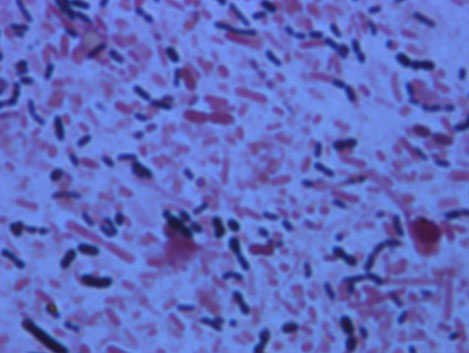

本学の医学科および工学資源学生、日赤看護大学の学生に、感染症学、渡航医学、感染制御学の講義を実施しています。このほか、グラム染色法の実習や、手指衛生の演習も行っています。